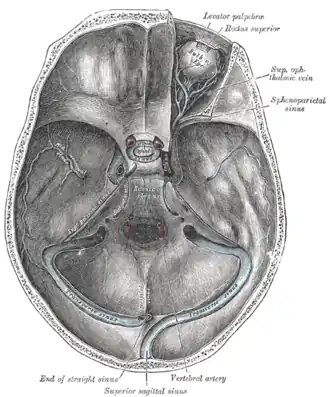

The sinuses at the base of the skull.

The sinuses at the base of the skull. -